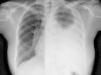

¿Sarcoidosis, tuberculosis o ambas?

Sarcoidosis, tuberculosis or both?